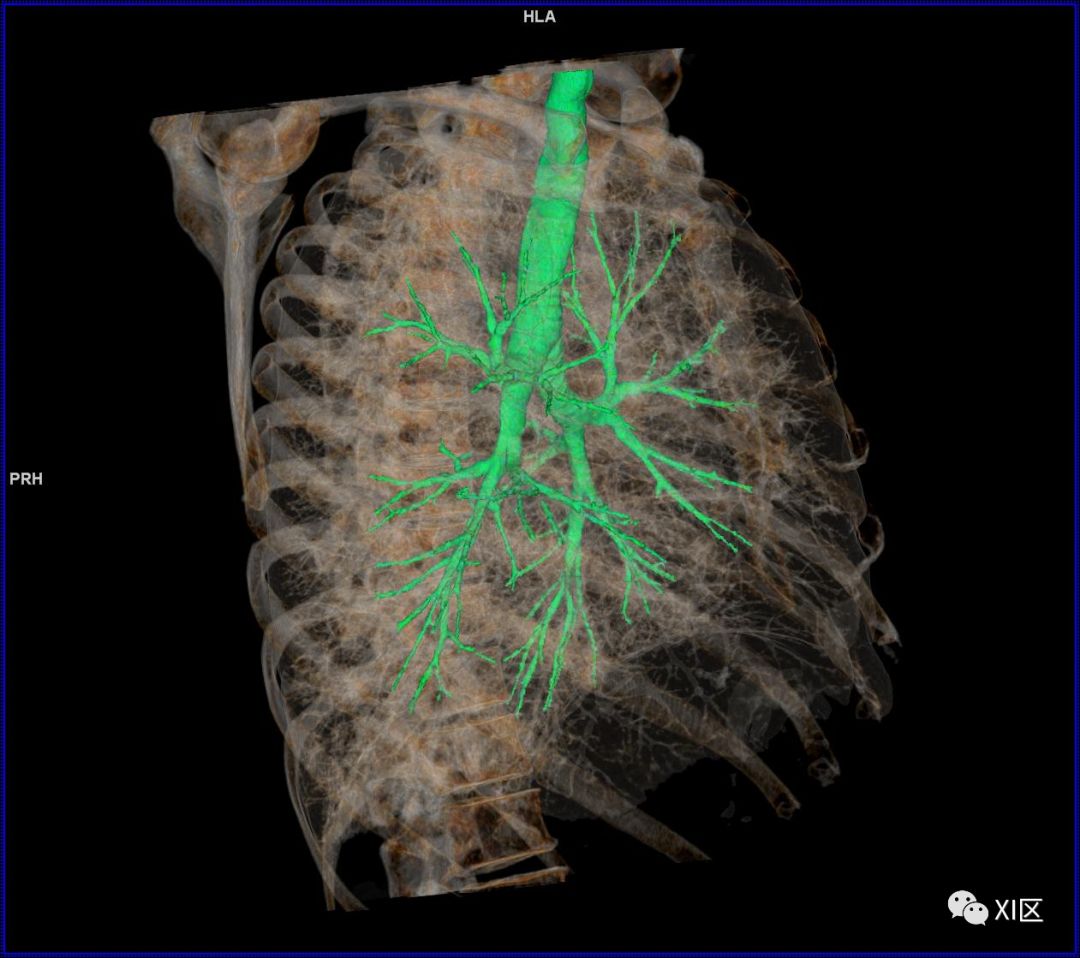

前后位,双侧位,后前位显示气道肺与胸部骨骼的关系

气管树与胸部其他结构的关系